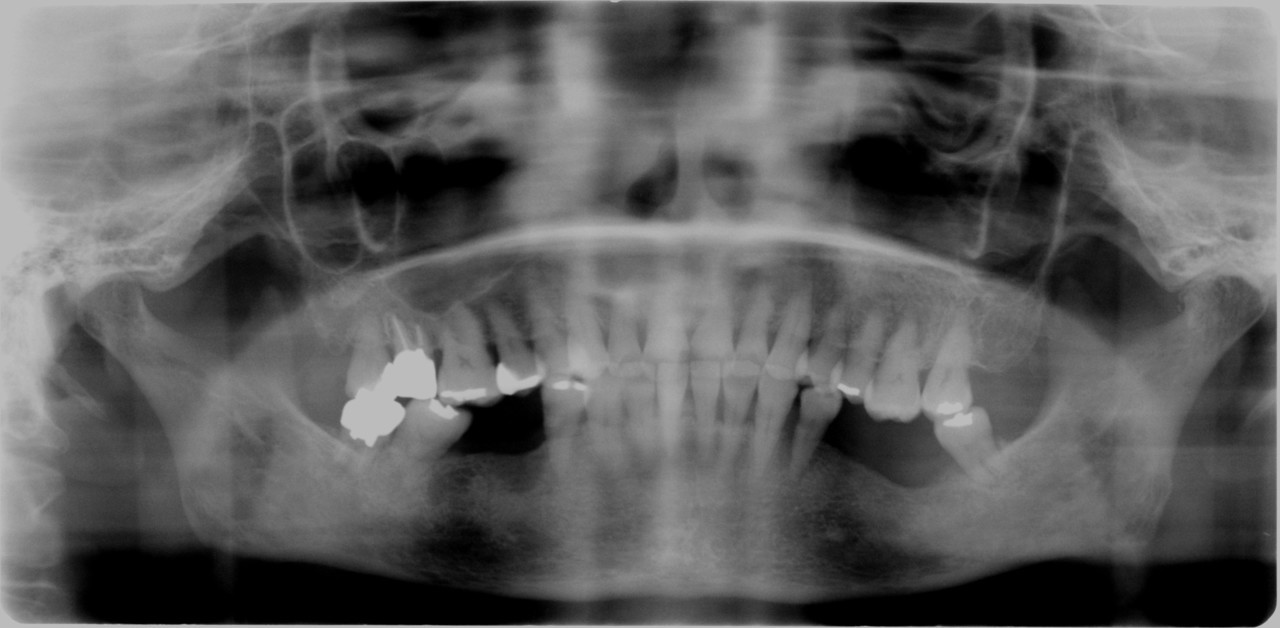

「脳梗塞の既往歴がある抗血小板薬

服用患者さんのインプラント症例 」

50代女性

奥歯を入れるにあたり、ブリッジ・義歯

インプラントを説明したところ インプラン

ト治療を希望

全身状態

• 既往歴として脳梗塞あり

• 現在抗血小板薬服用中

• インプラント前に出血傾向検査

出血は問題ないため抗血小板薬服用

状態でインプラント処置を行った。

治療期間 約2ヶ月

手術回数 1回

費用 150,000円(インプラント埋入処置費用)

29,000円(人工歯装着費用)